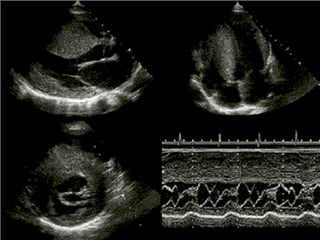

Etapas del estudio Confirmar diagnóstico (ECOC2D) Establecer etiología Establecer tipo de disfunción (sistólico o diastólico)  Establecer severidad Establecer causa descompensante Co - morbilidad

Etapas del estudioConfirmar diagnóstico (ECOC2D) Establecer etiología Establecer tipo de disfunción (sistólico o diastólico) Establecer severidad Establecer causa descompensante Co - morbilidad